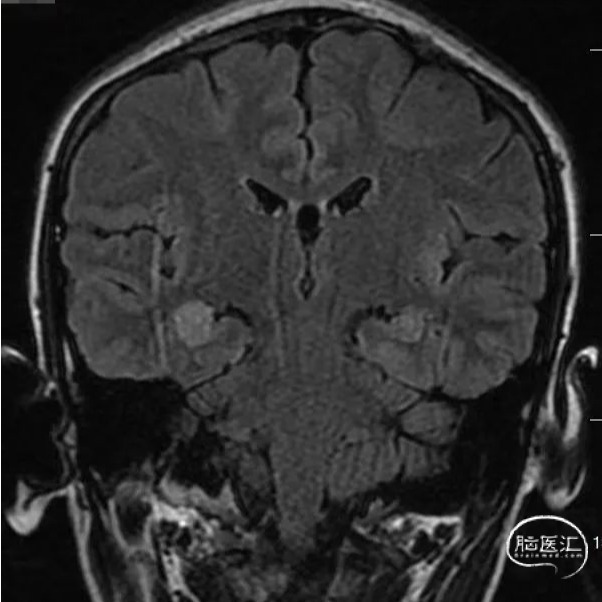

头颅MRI

头颅MR:双侧海马及杏仁核,双侧岛叶,左侧颞叶,双侧扣带回异常信号影。